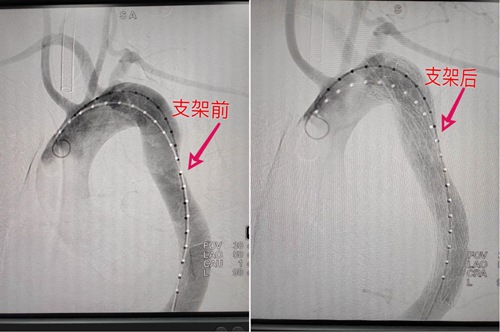

心内科主任许向东第一时间带领团队展开讨论,为患者制定治疗方案,最终确定了微创介入治疗——“主动脉造影+覆膜支架植入术”的手术方案,需要将覆膜支架放置在内膜破裂口,缓解下游躯体的灌注不足,预防夹层破裂,这样不开胸即可堵住血管裂口,即可拆除血管内的“定时炸弹”。

手术在心血管内科、麻醉科的通力合作下,仅用时一个半小时,过程十分顺利。术后患者恢复良好,一周后便康复出院。